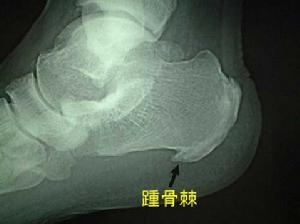

由於牽拉骨膜上的足底筋膜,跟骨下骨刺在早期形成階段可引起疼痛,雖然此時骨刺很小,甚至X線檢查也不能發現。隨著骨刺增大,疼痛常消失,這或許與足的適應性變化有關。因此X線上可見典型的骨刺可以沒有症狀。反過來,經過一段無症狀期以後,或由於局部外傷(如運動員損傷-參見第62節),骨刺可自發地產生疼痛。偶爾在局部形成外生滑囊,並引起炎症(跟骨下滑囊炎),引起足跟底部發熱跳痛。體格檢查時用拇指用力壓迫足跟中央可使疼痛加重。在踝背屈時,手指用力按壓整個筋膜內緣,有壓痛則證明存在筋膜炎。

儘管X線上發現有骨刺可作出診斷,但早期跟骨骨刺X線檢查可呈陰性結果。不常見的是,跟骨骨刺在X線上不典型,表現為絨毛狀新骨形成影像。見到此變化應考慮血清陰性或HLA-B27關節病(如強直性脊柱炎,賴特爾綜合徵)的可能。類風濕性關節炎和痛風是足跟痛的其他原因。這些關節痛常有中度到重度的發熱和腫脹,這一點可與局部原因所致的足跟痛相區別。